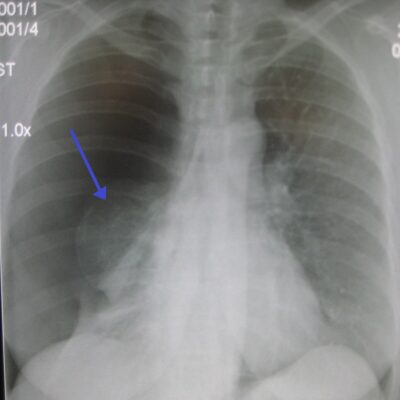

Παγκόσμιο συναγερμό έχει προκαλέσει η πνευμονία που «χτυπάει» τα παιδιά στην Κίνα, η οποία είναι γνωστή κι ως σύνδρομο του «λευκού πνεύμονα» και η οποία πλέον έχει κάνει την εμφάνισή της τόσο στις ΗΠΑ όσο και στην Ευρώπη.

Παρόμοια κρούσματα έχουν παρατηρηθεί στην Κίνα σε μεγαλύτερη κλίμακα, με αναπνευστικές ασθένειες όπως η γρίπη, οι ρινοϊοί και η πνευμονία από μυκόπλασμα, γνωστή και ως σύνδρομο λευκών πνευμόνων, να κυκλοφορούν στις κοινότητες.